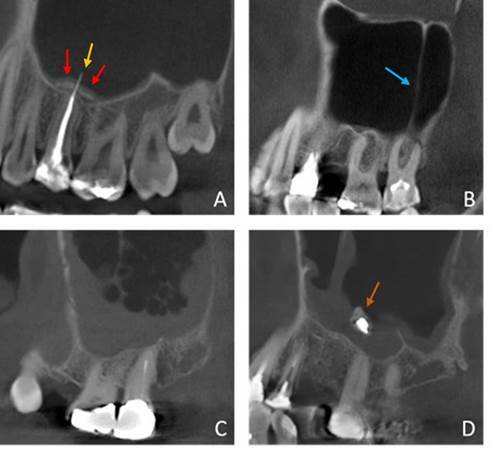

本研究旨在通过对锥形束计算机断层扫描(CBCT)图像进行回顾性分析,评估施奈德膜增厚与根尖周病理学之间的关系。为此,我们对包含 258 个窦和 1,181 颗牙齿的 147 张 CBCT 扫描图像进行了评估。硬膜层中断、牙周韧带间隙增宽、根尖牙周炎(AP)以及与 AP 相关的上颌窦底部分脱矿均被视为根尖周病变。上颌窦粘膜增厚(MSMT)分为牙源性和非牙源性。与病灶牙齿相关的不规则带状增厚和与牙根相关的局部增厚被认为是牙源性类型的 MSMT。根尖周病变的影像学特征与 MSMT 的类型和厚度之间的关系分别通过逻辑回归和线性混合模型来确定。此外,线性回归和曼-惠特尼检验评估了 AP 病变与窦底脱矿的关系(P≤0.05)。当上颌窦内存在根尖周病变时,发生牙源性 MSMT 的几率明显更高。82%的向窦底部分脱矿的 AP 与牙源性 MSMT 相关。这两种 AP 病变都部分向窦底脱矿,随着直径的增加,导致 MSMT 增加。总之,如果存在部分向窦底脱矿的 AP,则发生牙源性 MSMT 的风险为 82%。当 AP 病变较大且窦底部分脱矿时,上颌窦粘膜会增厚。

This study aimed to assess the relationship between Schneiderian membrane thickening and periapical pathology in a retrospective analysis of Cone Beam Computed Tomography (CBCT) images. For this, 147 CBCT scans containing 258 sinuses and 1,181 teeth were assessed. Discontinuation of the lamina dura, widening of the periodontal ligament space, apical periodontitis (AP), and partly demineralized maxillary sinus floor associated with AP were considered periapical pathology. Maxillary sinus mucosal thickening (MSMT) was classified as odontogenic or non-odontogenic. An irregular band with a focal tooth associated thickening and local thickening related to a root were considered odontogenic types of MSMT. The relation between the imaging features of periapical pathology and the type and thickness of MSMT was determined by logistic regression and linear mixed model, respectively. In addition, linear regression and Mann Whitney test evaluated the relation and demineralization of the AP lesion towards the sinus floor (p≤0.05). The odds of having an odontogenic type of MSMT were significantly higher when a periapical pathology was present in the maxillary sinus. Eighty-two percent of AP partly demineralized towards the sinus floor were associated with an odontogenic MSMT. Both AP lesions partly demineralized towards the sinus floor and, with increased diameter, led to increased MSMT. In conclusion, there is an 82% risk of having an odontogenic type of MSMT with the presence of AP partly demineralized towards the sinus floor. More thickening of the maxillary sinus mucosa is seen with larger AP lesions and partial demineralization of the sinus floor.